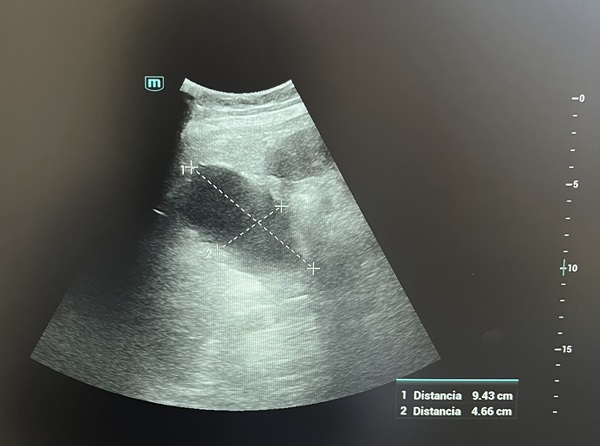

Descripción de los hallazgos ecográficos y las imágenes más relevantes para la resolución del caso

Vesícula biliar ligeramente distendida de 8,5 x 5 cm sin presencia de colelitiasis en su interior; impresionando dilatación de vía biliar intra y extrahepática.

Se realiza AS bilirrubina 7,46 mg/dL, GGT: 935 y FA: 329. Amilasa y lipasa normales. No leucocitosis. PCR: 56,5. Datos de infección de orina con leucocituria y nitritos positivos. Screening Treponémico negativo. Realizan ecografía abdominal confirmando los hallazgos anteriormente descritos, además de esplenomegalia de 12,5 cm y probable trombosis de la vena porta principal. Se ingresa con antibioticoterapia empírica por foco urinario y para completar estudio. TC abdomino-pélvico: tumoración de aspecto infiltrativo en hilio hepático, de 3,3 x 6,3 x 5,6 que infiltra la vena porta y el colédoco, con adenopatías asociadas. Metástasis hepáticas, dudoso implante peritoneal. Nódulo en cuadrante inferointerno de mama izquierda.